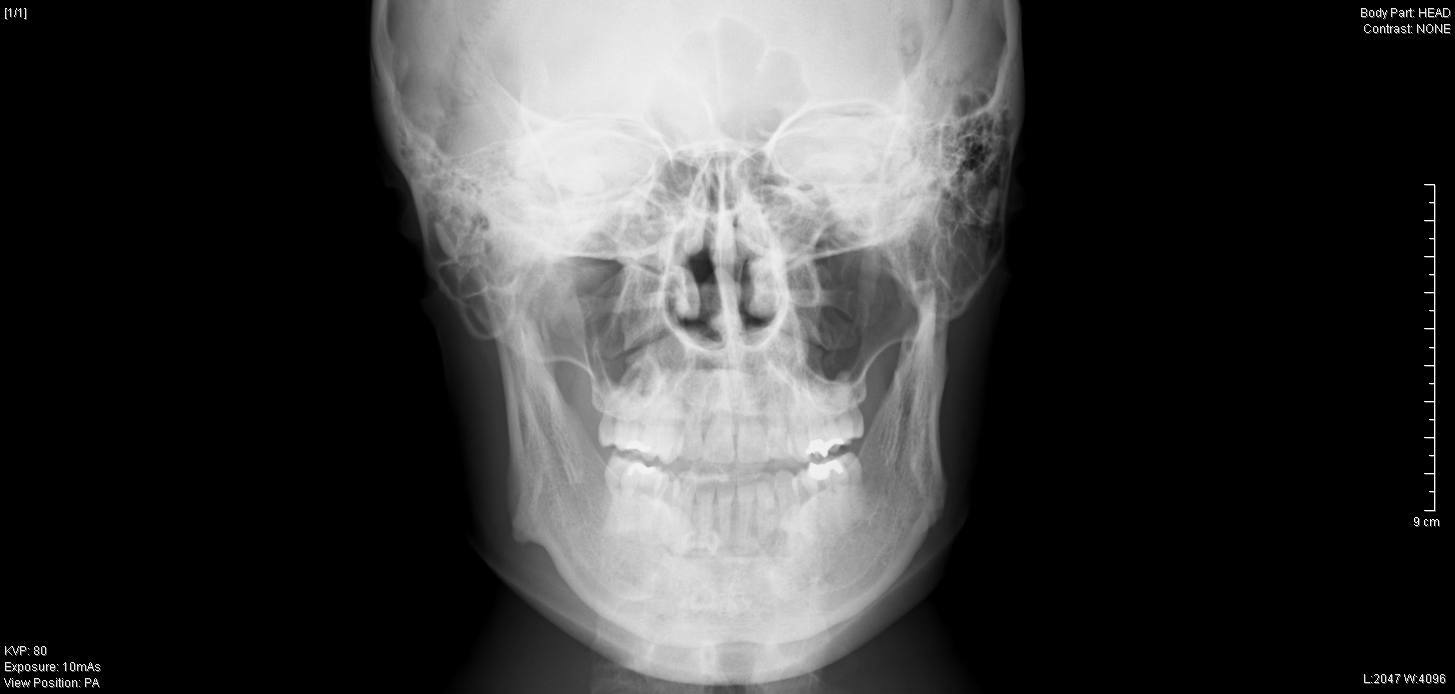

【骨切り手術前 正面】

レントゲンでは、上下方向の切除幅は約1cm、

それに加えEラインを考慮して、

右側 最大 10mm

左側 最大 9mm

先端部 7mm